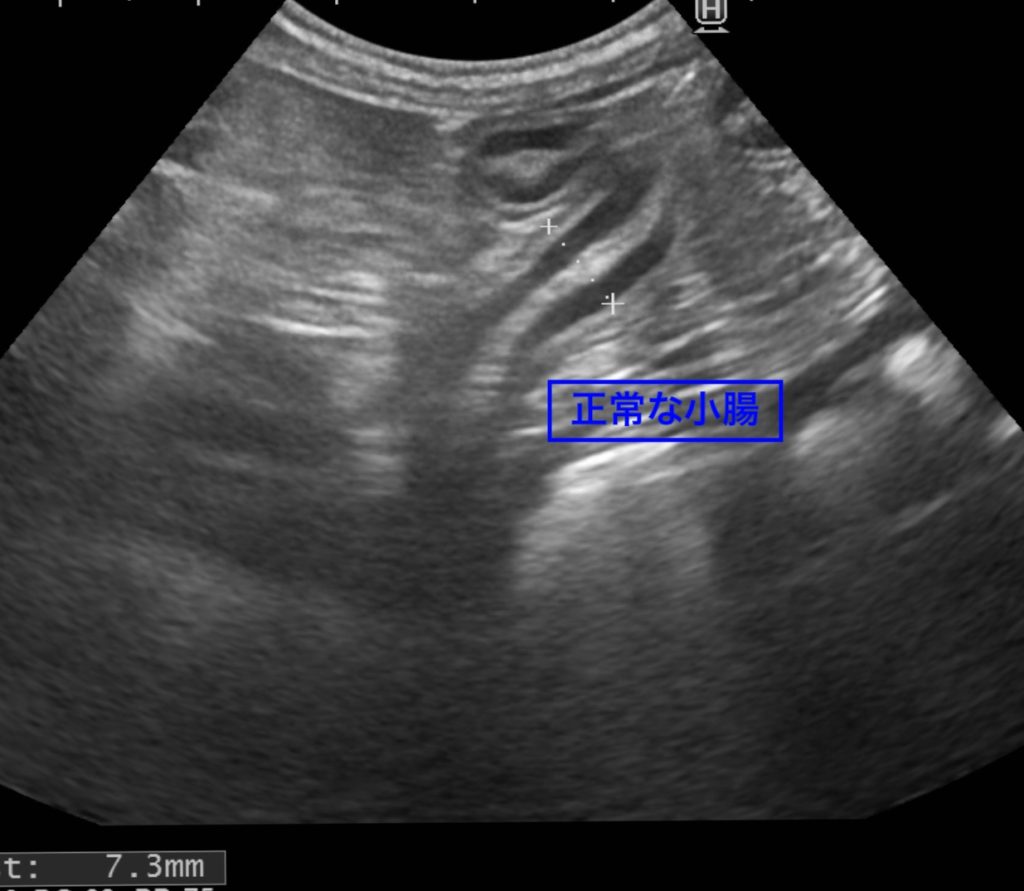

正常な小腸については、犬種による差がありますが、概ね6~7mmほどの直径のことが多いです。

白い部分に食べ物が流れ、そこを取り囲むように黒い粘膜が覆っています。